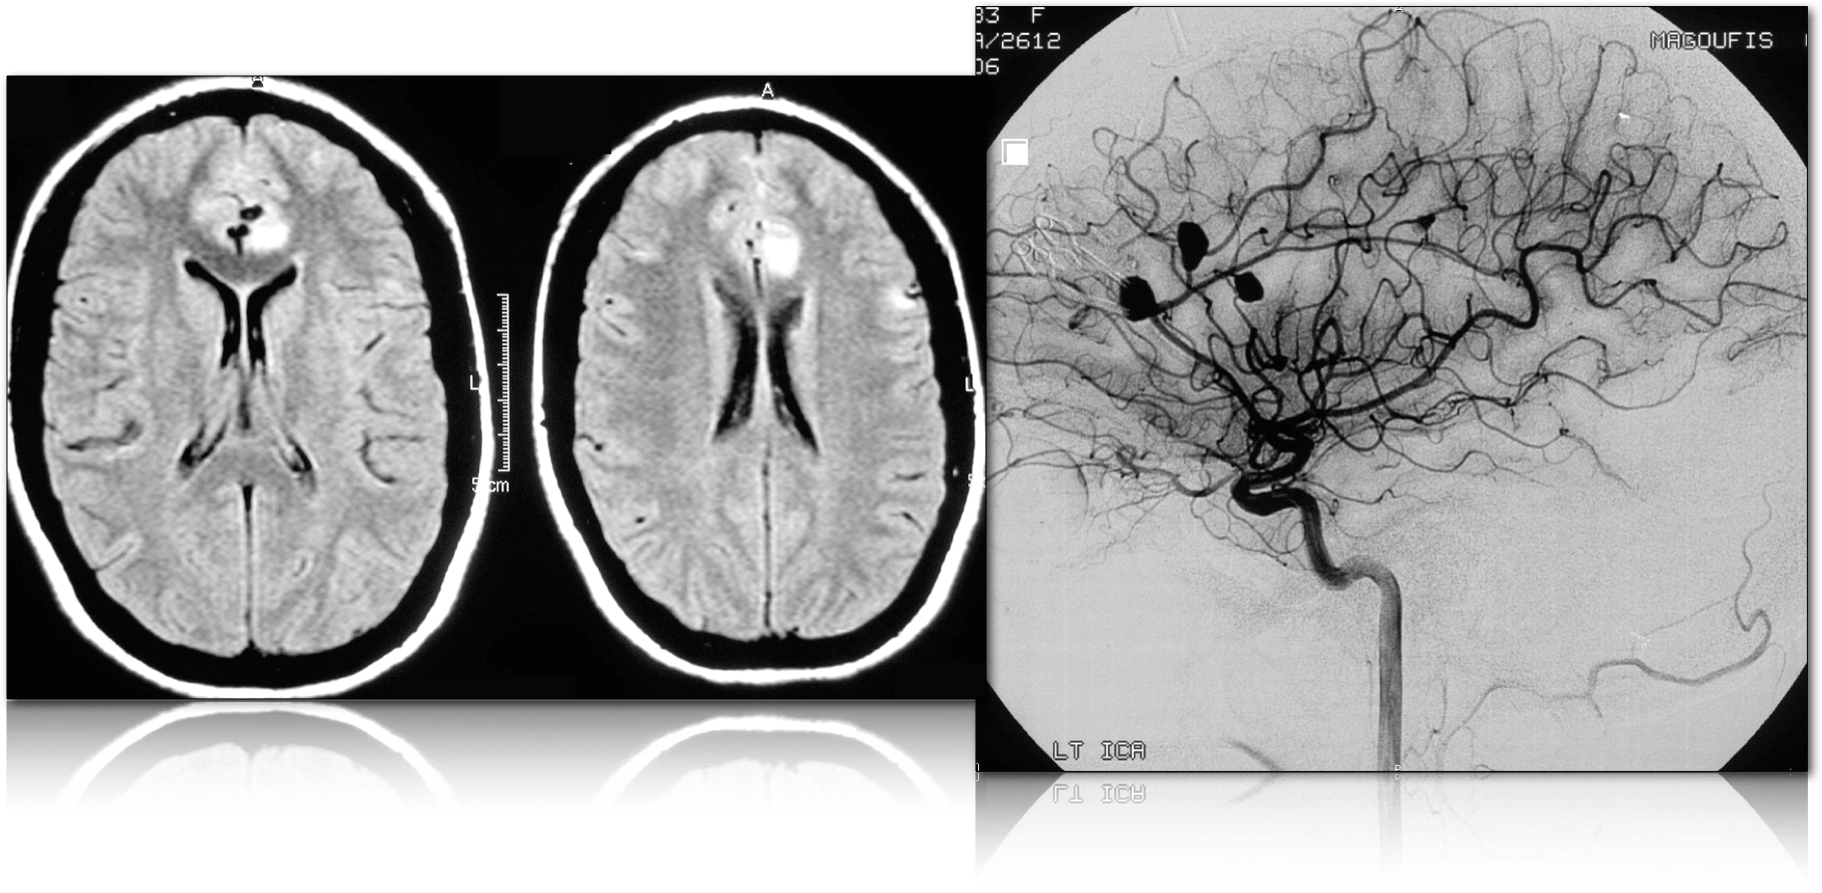

Tά ενδοκράνια ανευρύσματα συμβαίνουν συνήθως στα σημεία διχασμού των αρτηριών, κατά την υπαραχνοειδή πορεία τους γύρω το εξάγωνο του Willis.

Ταξινομούνται με βάση την μορφολογία τους σε σακοειδή και ατρακτοειδή. Tα σακκοειδή είναι τα συχνότερα (80-90%) περιλαμβάνουν τμήμα της περιφέρειας της αρτηρίας με την οποία επικοινωνούν με τον αυχένα, ενώ στά ατρακτοειδή που είναι σπανιώτερα, συμμετέχει ολόκληρη η περιφέρεια της αρτηρίας και δεν έχουν αυχένα.

Υπάρχουν επίσης τα μυκωτικά ή φλεγμονώδη ανευρύσματα που είναι συχνά σε ασθενείς με λοιμώδη ενδοκαρδίτιδα και άτομα που κάνουν χρήση ναρκωτικών ουσιών. Τυπικά δημιουργούνται περιφερικότερα του εξαγώνου του Willis, συνήθως είναι πολλαπλά και αντιμετωπίζονται συντηρητικά με αντιβιοτικά και φαρμακευτική αγωγή. Ο εμβολισμός αποτελεί αντένδειξη.